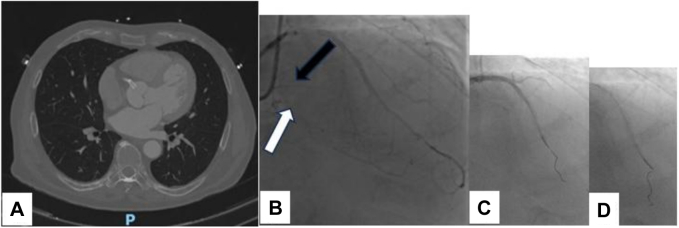

Figure 2.

Initial Phase of Our Attempt

(A) CT scan showing right sinus hematoma with an ostial protruding stent. (B, D) Good result of LAD PCI and occlusion of the DP (white arrow) and PL (black arrow) branches as demonstrated by heterocoronary collateralization (B); third tortuous septal surfing (C). CT = computed tomography; DP = descending posterior artery; LAD = left anterior descending artery; PCI = percutaneous coronary intervention; PL = posterolateral artery.